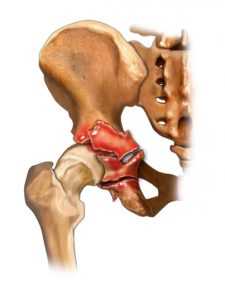

Рис — Анатомия костей таза

В образовании вертлужной впадины принимают участие три кости: подвздошная, лобковая и седалищная. Соединившись вместе, они образуют тазовую кость, а вместе их сочленения — суставную впадину тазобедренного сустава. Сформировавшаяся ямка приобретает форму полусферы, суставная поверхность вертлужной впадины углубляется с помощью хряща, расположенного по краю полусферы в виде ободка.

Вертлужная впадина состоит из передней стенки, задней стенки и дна. Суставная поверхность бедренной кости связкой крепится к центру суставной впадины

Рис — Переломы вертлужной впадины